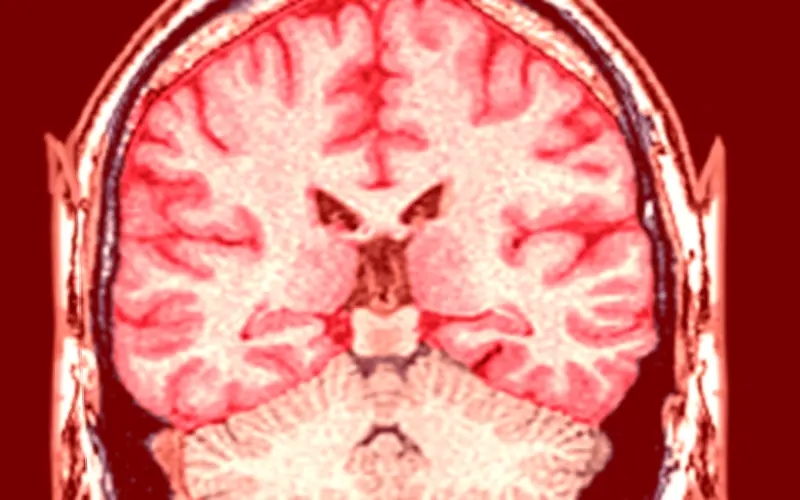

Infartos cerebrales en adultos jóvenes: la crisis silenciosa que crece en México

Los infartos cerebrales, conocidos médicamente como accidentes cerebrovasculares (ACV), han dejado de ser una amenaza exclusiva de la tercera edad. En la actualidad, las salas de urgencias en México y a nivel global están recibiendo cada vez a más pacientes que apenas superan los 30 años de edad, un dato que alarma profundamente a los expertos en salud neurológica. Este fenómeno representa un cambio drástico en la epidemiología moderna, obligando a la comunidad médica a replantear urgentemente sus estrategias de prevención.